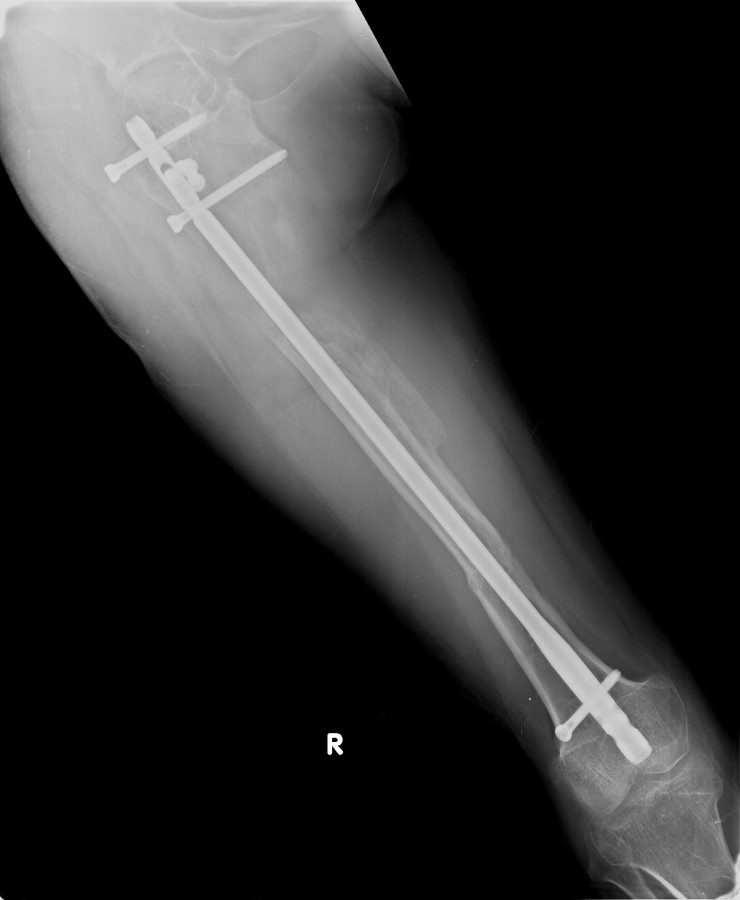

Vaka 2